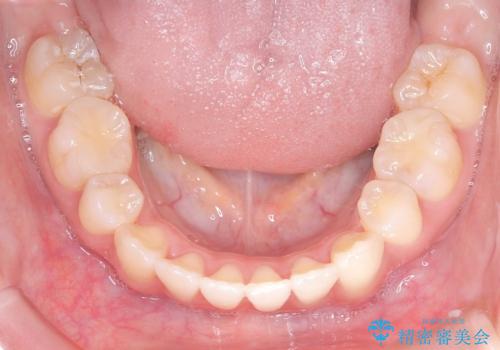

【インビザライン】シザーズバイト、抜歯矯正

- オープンバイトを主訴に来院された患者様です。

抜歯を行うことで、インビザラインを用いて前歯を下げることができ、同時にオープンバイトを改善することができました。

今回はインビザラインのみで治療を終了することができました。